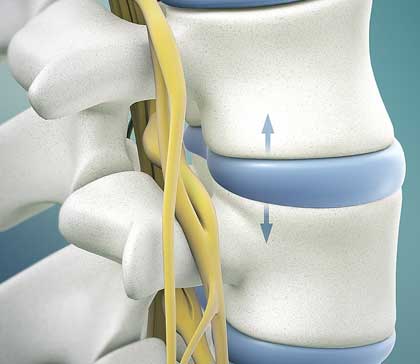

The bones (vertebrae) that form the spine in the back are cushioned by discs. These discs are round, like small pillows, with a tough, outer layer (annulus) that surrounds the nucleus. Located between each of the vertebra in the spinal column, discs act as shock absorbers for the spinal bones.

A herniated disc (also called bulged, slipped or ruptured) is a fragment of the disc nucleus that is pushed out of the annulus, into the spinal canal through a tear or rupture in the annulus. Discs that become herniated usually are in an early stage of degeneration. The spinal canal has limited space, which is inadequate for the spinal nerve and the displaced herniated disc fragment. Due to this displacement, the disc presses on spinal nerves, often producing pain, which may be severe.